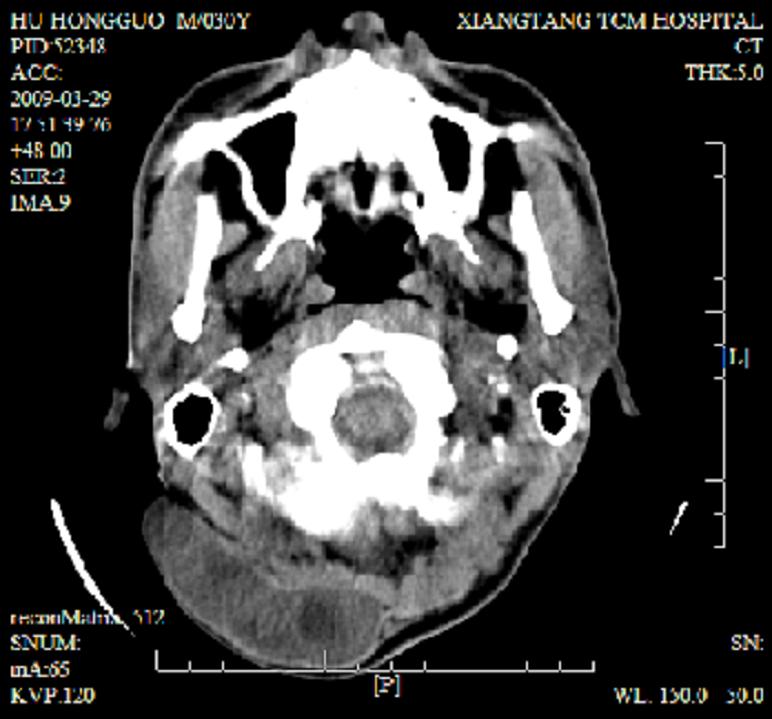

标题: CT19102:颈部肿块

男30y发现肿块3年

多处囊实性肿块,形态欠规则有一定形态,内见点状钙化,以囊变为主,增强后轻度强化,首先考虑神经源性肿瘤如鞘瘤,不除外脉管源性肿瘤如淋巴管瘤(见缝钻及囊性区域太多,如果合并感染完全可以这个影像表现),和海绵状血管瘤,但是血管瘤不太支持因为强化特征和病灶形态不典型.

右侧椎前间隙后部肌间、皮下囊性为主病变,可见分隔和点状钙化,分隔和壁呈轻度环形强化,大部分无强化。形态不规则,有钻缝特点。考虑1 淋巴管瘤合并感染2 血管平滑肌脂肪瘤3 表皮样囊肿4 不除外海绵状血管瘤。

病灶沿皮下及肌间隙爬行,病灶内有钙化灶,病灶有强化。病史3年,病人应该没什么症状。考虑纤维血管瘤可能性大。